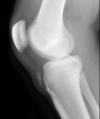

Motor: great toe extension

Tibial spine fracture (intercondylar eminence) **associated with ACL rupture More common in children MOI- twisting knee movement, hyperflexion, hyperextension Immediate pain and swelling after injury XR: There is an avulsion fracture (red and white arrows) of the intercondylar eminence. There is a also a large suprapatellar hemarthrosis (yellow arrow). Such fractures are associated with injury to the anterior cruciate ligament.